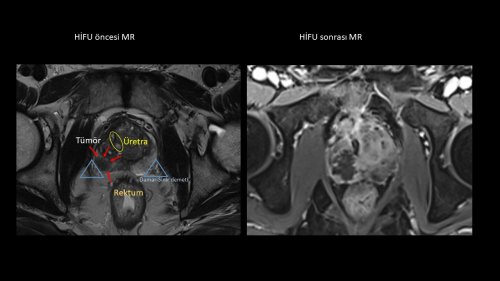

HİFU yönteminin hastaya işlem sonrasında da birçok avantaj sağladığını kaydeden Prof. Dr. Turna, “Bu yöntemde cihazının ultrason probunun görüntüleri ile MR görüntüleri bilgisayarda birleştirilerek kanserli bölge işaretleniyor. Böylece cinsel fonksiyon bozukluğuna sebep olabilecek damar ve sinirlerin tahribatına yol açmadan operasyon tamamlanıyor. Vücutta herhangi bir travma oluşmadığı için hastanın günlük yaşama ve iş başına dönme süresi de kısalıyor. Yöntem sayesinde klasik cerrahi işlemlere gerek kalmadan başarılı sonuçlar alabiliyoruz” diye konuştu.

Uzm. Dr. Kısmalı, şöyle devam etti: “Cerrahi bir işlem yapılmadan, prostat kanserli olan bölgeye, makat yoluyla gönderilen ultrasonik enerji, MR ve Ultrason görüntülerinin bilgisayarda hedeflediği bölgeyi içten ısıtarak canlılığını ortadan kaldırmaktadır. Keskin sınırlarla odaklanabilen ultrasonik ısıtıcı enerjiyle, yan etkilerin ortaya çıkmasına neden olan damar-sinir demeti ve idrar yolları olabildiğince güvenli şekilde korunmaktadır. Tüm enerji yalnızca kanserli hücreleri yok edecek şekilde yönlendirilebilmekte ve odak sınırları sürekli kontrol edilebilmektedir. Seçilmiş uygun hastalara, kesi ve dikiş olmaksızın uygulanabilen HİFU yöntemiyle, klasik cerrahi yöntemlerden sonra görülebilen kalıcı ciddi yan etkiler daha az yaşanmakta, cerrahiye bağlı konforsuz dönem kısalmakta ve daha hızlı iyileşme ile günlük hayata kısa sürede geri dönülebilmektedir. HİFU, gerektiğinde aynı hastada veya önceki başka klasik yöntemlerden sonra, güvenle tekrarlanabilir”